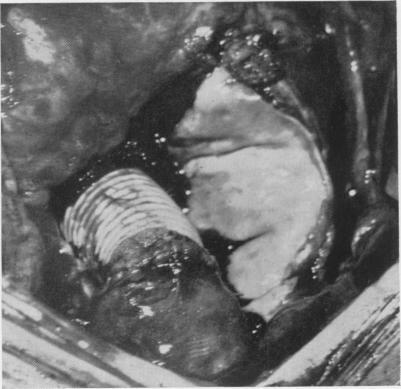

THE SURGICAL TREATMENT OF DISSECTING ANEURYSM OF THE ASCENDING AORTA: WITH A REPORT OF FOUR CASES IN THE CHRONIC STAGE.

Ann Surg. 1964 Jun;159(6):829-45. doi: 10.1097/00000658-196406000-00002.